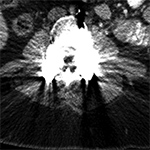

Streak and Shadow Artifact. (A) Axial CT image of the lumbar spine demonstrates extensive high attenuation linear streak and splay artifact secondary to posterior spinal fusion hardware.  (B) Axial CT image of the left hip demonstrates linear low attention shadow artifact propagating along the axis of greatest metal cross-section, which obscures the femoral neck.